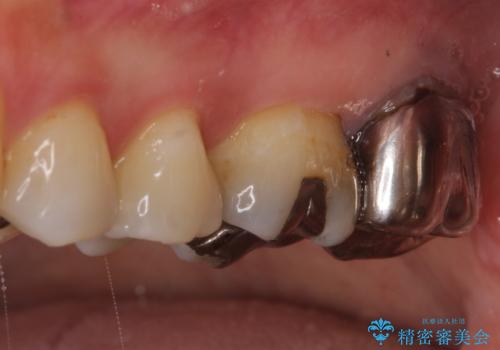

【根管治療】未処置根管を有した歯の再根管治療

- 定期検診にて虫歯を見つけたため、根管治療からオールセラミッククラウンによる修復治療を行いました。

レントゲンにて透過像を認めている上顎第二大臼歯も治療予定です。

上顎第一大臼歯の近心根にはほとんどの場合、神経の管が二本あることが多いです。顕微鏡を用いることで見逃すことなく治療が行えました。